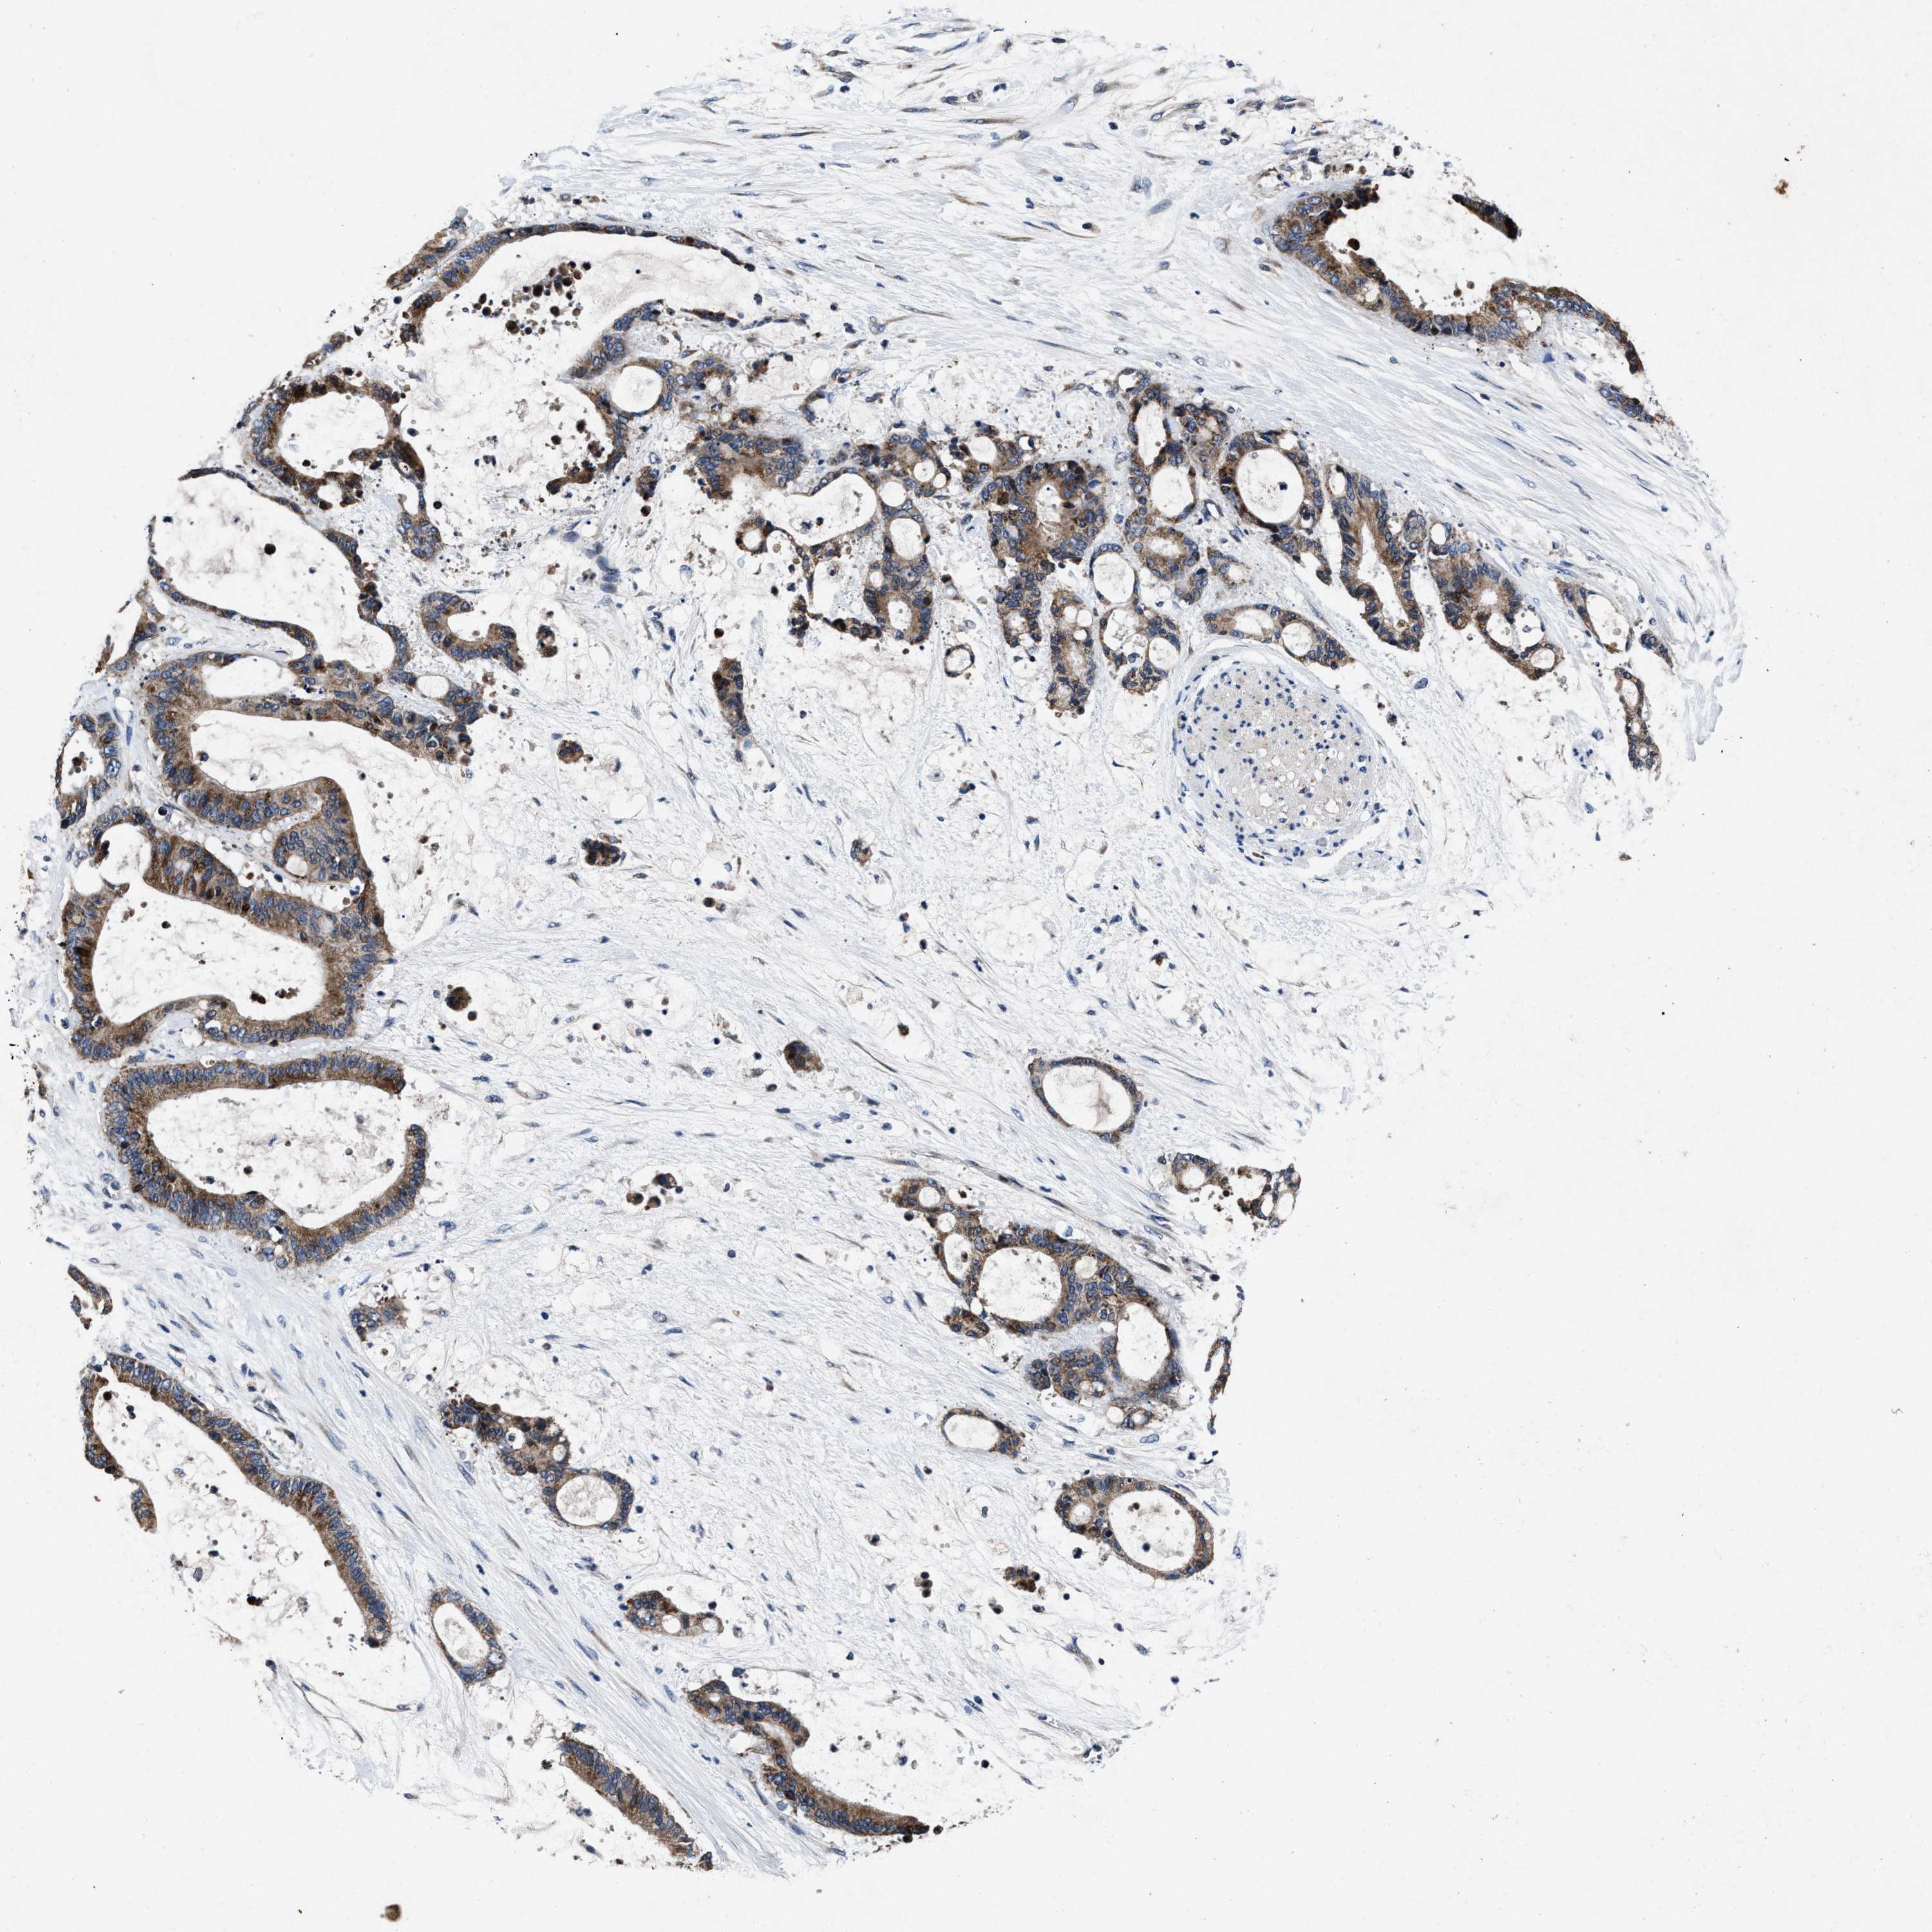

LIVER CANCER - Protein expressioni

A mouse-over function shows sample information and annotation data. Click on an image to view it in a full screen mode. Samples can be filtered based on level of antibody staining by selecting one or several of the following categories: high, medium, low and not detected. The assay and annotation is described here.

Note that samples used for immunohistochemistry by the Human Protein Atlas do not correspond to samples in the TCGA dataset.

Antibody stainingi

Antibody staining in the annotated cell types in the current human tissue is reported as not detected, low, medium, or high, based on conventional immunohistochemistry profiling in selected tissues. This score is based on the combination of the staining intensity and fraction of stained cells.

Each image is clickable and will lead to virtual microscopy that enables deeper exploration of all samples and also displays staining intensity scores, fraction scores and subcellular localization as well as patient and tissue information for each sample.

Antibody HPA021134

Staining

High

Medium

Low

Not detected

Intensity

Strong

Moderate

Weak

Negative

Quantity

>75%

75%-25%

<25%

None

Location

Nuclear

Cytoplasmic/membranous

Cytoplasmic/membranous,nuclear

Cholangiocarcinoma

Carcinoma, Hepatocellular, NOS